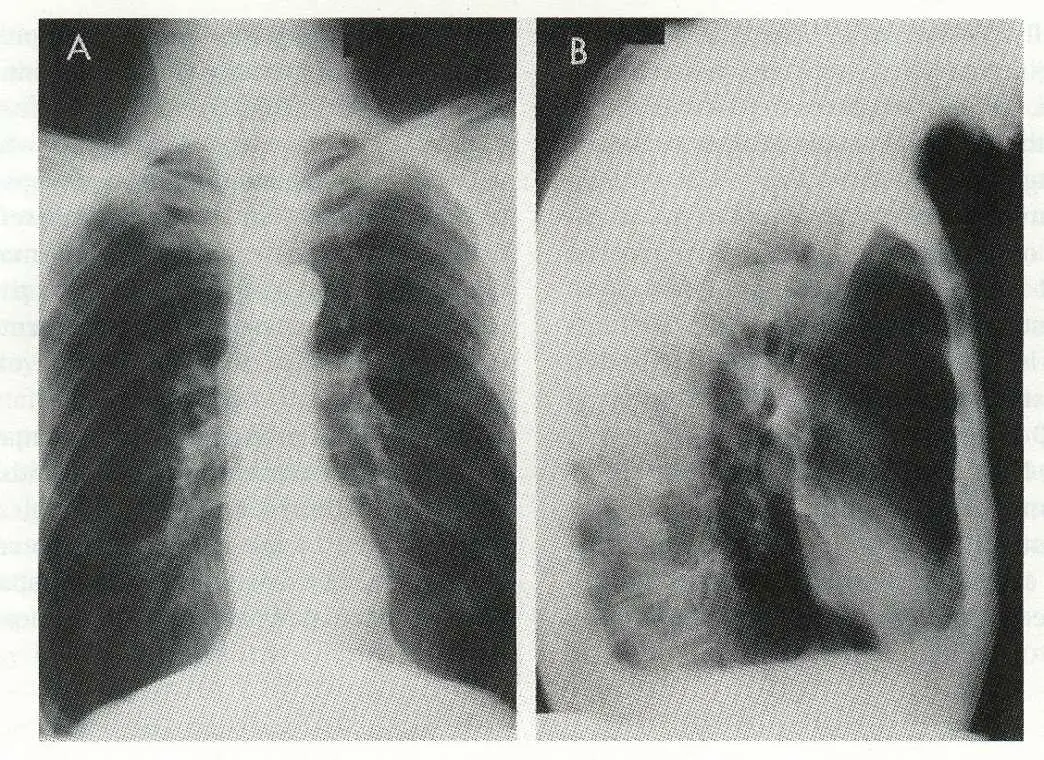

某病人的胸腔 X光如下圖,其診斷應為何?

本題提供兩張胸腔 X 光影像(後前位 PA view 與側位 lateral view):

後前位(PA view,左圖):

- 雙側肺野明顯透亮度增加(hyperlucency),肺野擴大

- 橫膈膜(diaphragm)明顯扁平化(flattening),位置偏低

- 肋骨呈水平走向(horizontal ribs),肋間隙增寬

- 心臟輪廓相對狹窄(narrow cardiac silhouette),呈「水滴心」外觀

- 肺紋理(vascular markings)明顯減少,肺周邊更為透亮

- 以上表現符合典型肺氣腫之肺部過度膨脹

側位(Lateral view,右圖):

- 胸骨後間隙(retrosternal airspace)明顯增加

- 橫膈膜弓形消失,幾乎呈完全扁平

- 前後徑(AP diameter)增加,呈「桶狀胸(barrel chest)」形態